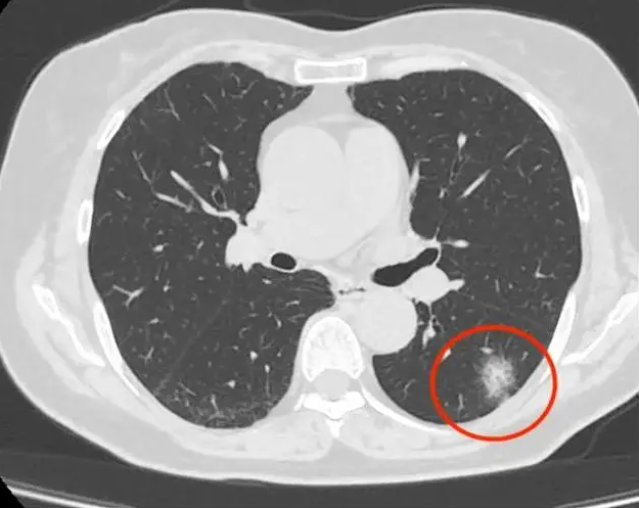

肺部阴影是影像学检查如CT或X光中发现的肺部异常密度区域,可能由多种疾病引起,需结合进一步检查明确性质1 肺部炎症常见于细菌病毒或支原体感染引发的肺炎炎症导致肺部组织充血水肿,形成片状或斑片状阴影,多伴有发热咳嗽咳痰等症状及时使用抗生素或抗病毒药物后,阴影通常可逐渐吸收2。

肺部出现白色阴影可能是多种疾病的表现,常见原因包括肺炎肺结核肺癌和肺水肿,具体如下肺炎由细菌病毒或真菌等病原体感染肺部引发炎症影像学上,白色阴影通常因肺泡内充满炎性渗出物如脓液细胞碎片而形成,表现为片状或斑片状密度增高影患者常伴咳嗽发热呼吸困难等症状,血常规可能。

1 肺部感染性疾病 肺炎由病原微生物引起的肺部感染,X线表现为片状阴影,伴有咳嗽咳痰发烧等症状 肺结核由结核杆菌引起的肺部感染,阴影表现为散在的片絮状或球形病灶,患者常有咳嗽咯血及结核中毒症状 支气管扩张支气管壁的化脓性感染,X线表现为肺纹理增多增粗紊乱,严重时可。

肺部絮状阴影并非特指某一种具体的疾病,而是肺部在胸片或CT检查上呈现出的一种影像学表现,可能由多种疾病导致以下是可能导致肺部絮状阴影的几种情况肺部感染性疾病肺结核年轻患者,出现咳嗽痰量不多咯血等症状时,如果肺部有絮状阴影,要考虑结核杆菌感染导致的肺结核细菌性肺炎患者全身。